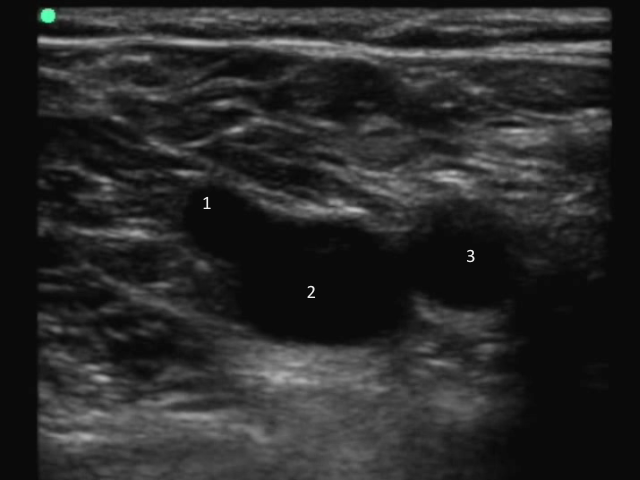

DVT:图像 1 带标记的 CFV 隐静脉汇合处